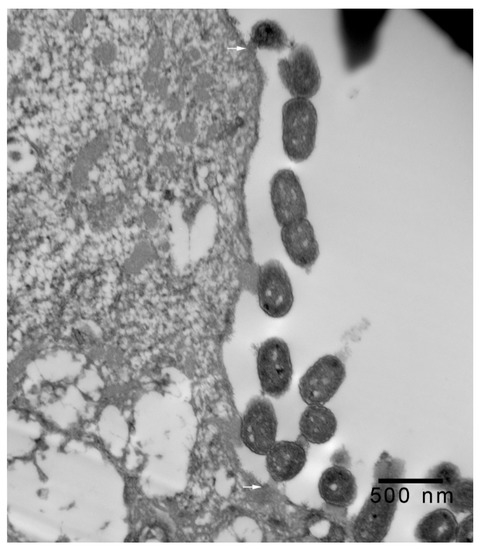

In 1-μm thick Araldite sections of urinary bladder prepared from tissues originally contained within the paraffin blocks [25], bacteria were detected only in piglet 15627 (Figure 1). In this piglet, in which bladder sections were oriented such that all three cell layers (basal, intermediate and superficial or umbrella) of the urothelium [26,27,28,29] were visible, bacteria, corresponding to bovine-origin strain 2891, were diffusely adherent to the apical surfaces of umbrella cells. By TEM, bacterial cells were found intimately attached to pedestals (Figure 2, Figure 3 and Figure 4). Some bacterial cells appeared to be attached to microplicae, preceding pedestal formation (Figure 4).

Figure 1.

Light photomicrograph of toluidine blue-stained, 1-μm thick, Araldite section of urinary bladder of piglet 15627, 8 days post-inoculation (PI) with bovine-origin strain 2891. EHEC O157:H7 bacterial cells (arrows) are diffusely attached to the apical surfaces of superficial uroepithelial (umbrella; U) cells. The section includes all layers of the mucosa, with U cells, intermediate cells (I) and basal cells (B) present, as has been described in pigs [26,27], humans [28], and other species [29]. Basal lamina (BL) and submucosa with structures such as blood vessels (BV) are also seen in the section. Photomicrographs stained with hematoxylin and eosin (H&E) showing purulent cystitis, and positive immunohistochemical staining for E. coli O157 antigen of a larger sample of the same piglet specimen were shown in the previous publication [25]. Bar = 5 μm.